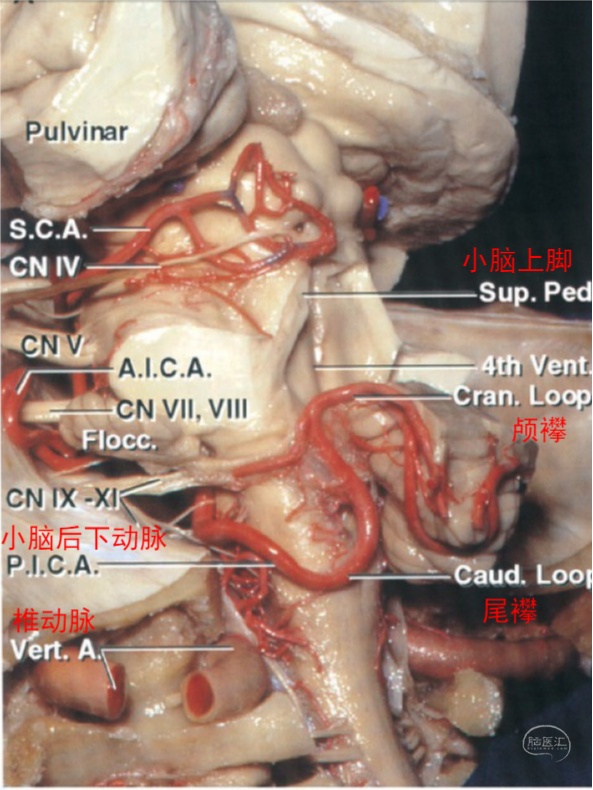

图2 小脑后下动脉后外侧面观。延髓前段、延髓外侧段、扁桃体延髓段发出穿支动脉进入延髓前面、外侧面和后面,这些穿支动脉可在延髓表面与椎动脉V4段发出的穿支动脉形成吻合。扁桃体延髓段和膜帆扁桃体段可发出脉络膜动脉供应四脑室脉络丛。